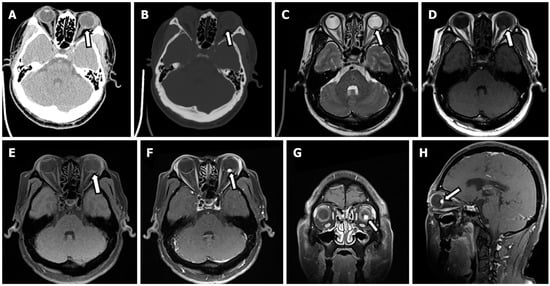

- Halefoglu, A.M. Von Hippel-Lindau Disease Presenting with Cranial and Spinal Hemangioblastomas: MRI Findings. Acta Med. Iran 2023, 61, 115–117. [Google Scholar] [CrossRef]

- Mehta, G.U.; Kim, H.J.; Gidley, P.W.; Daniels, A.B.; Miller, M.E.; Lekovic, G.P.; Butman, J.A.; Lonser, R.R. Endolymphatic Sac Tumor Screening and Diagnosis in von Hippel-Lindau Disease: A Consensus Statement. J. Neurol. Surg. B Skull Base 2022, 83, e225–e231. [Google Scholar] [CrossRef]